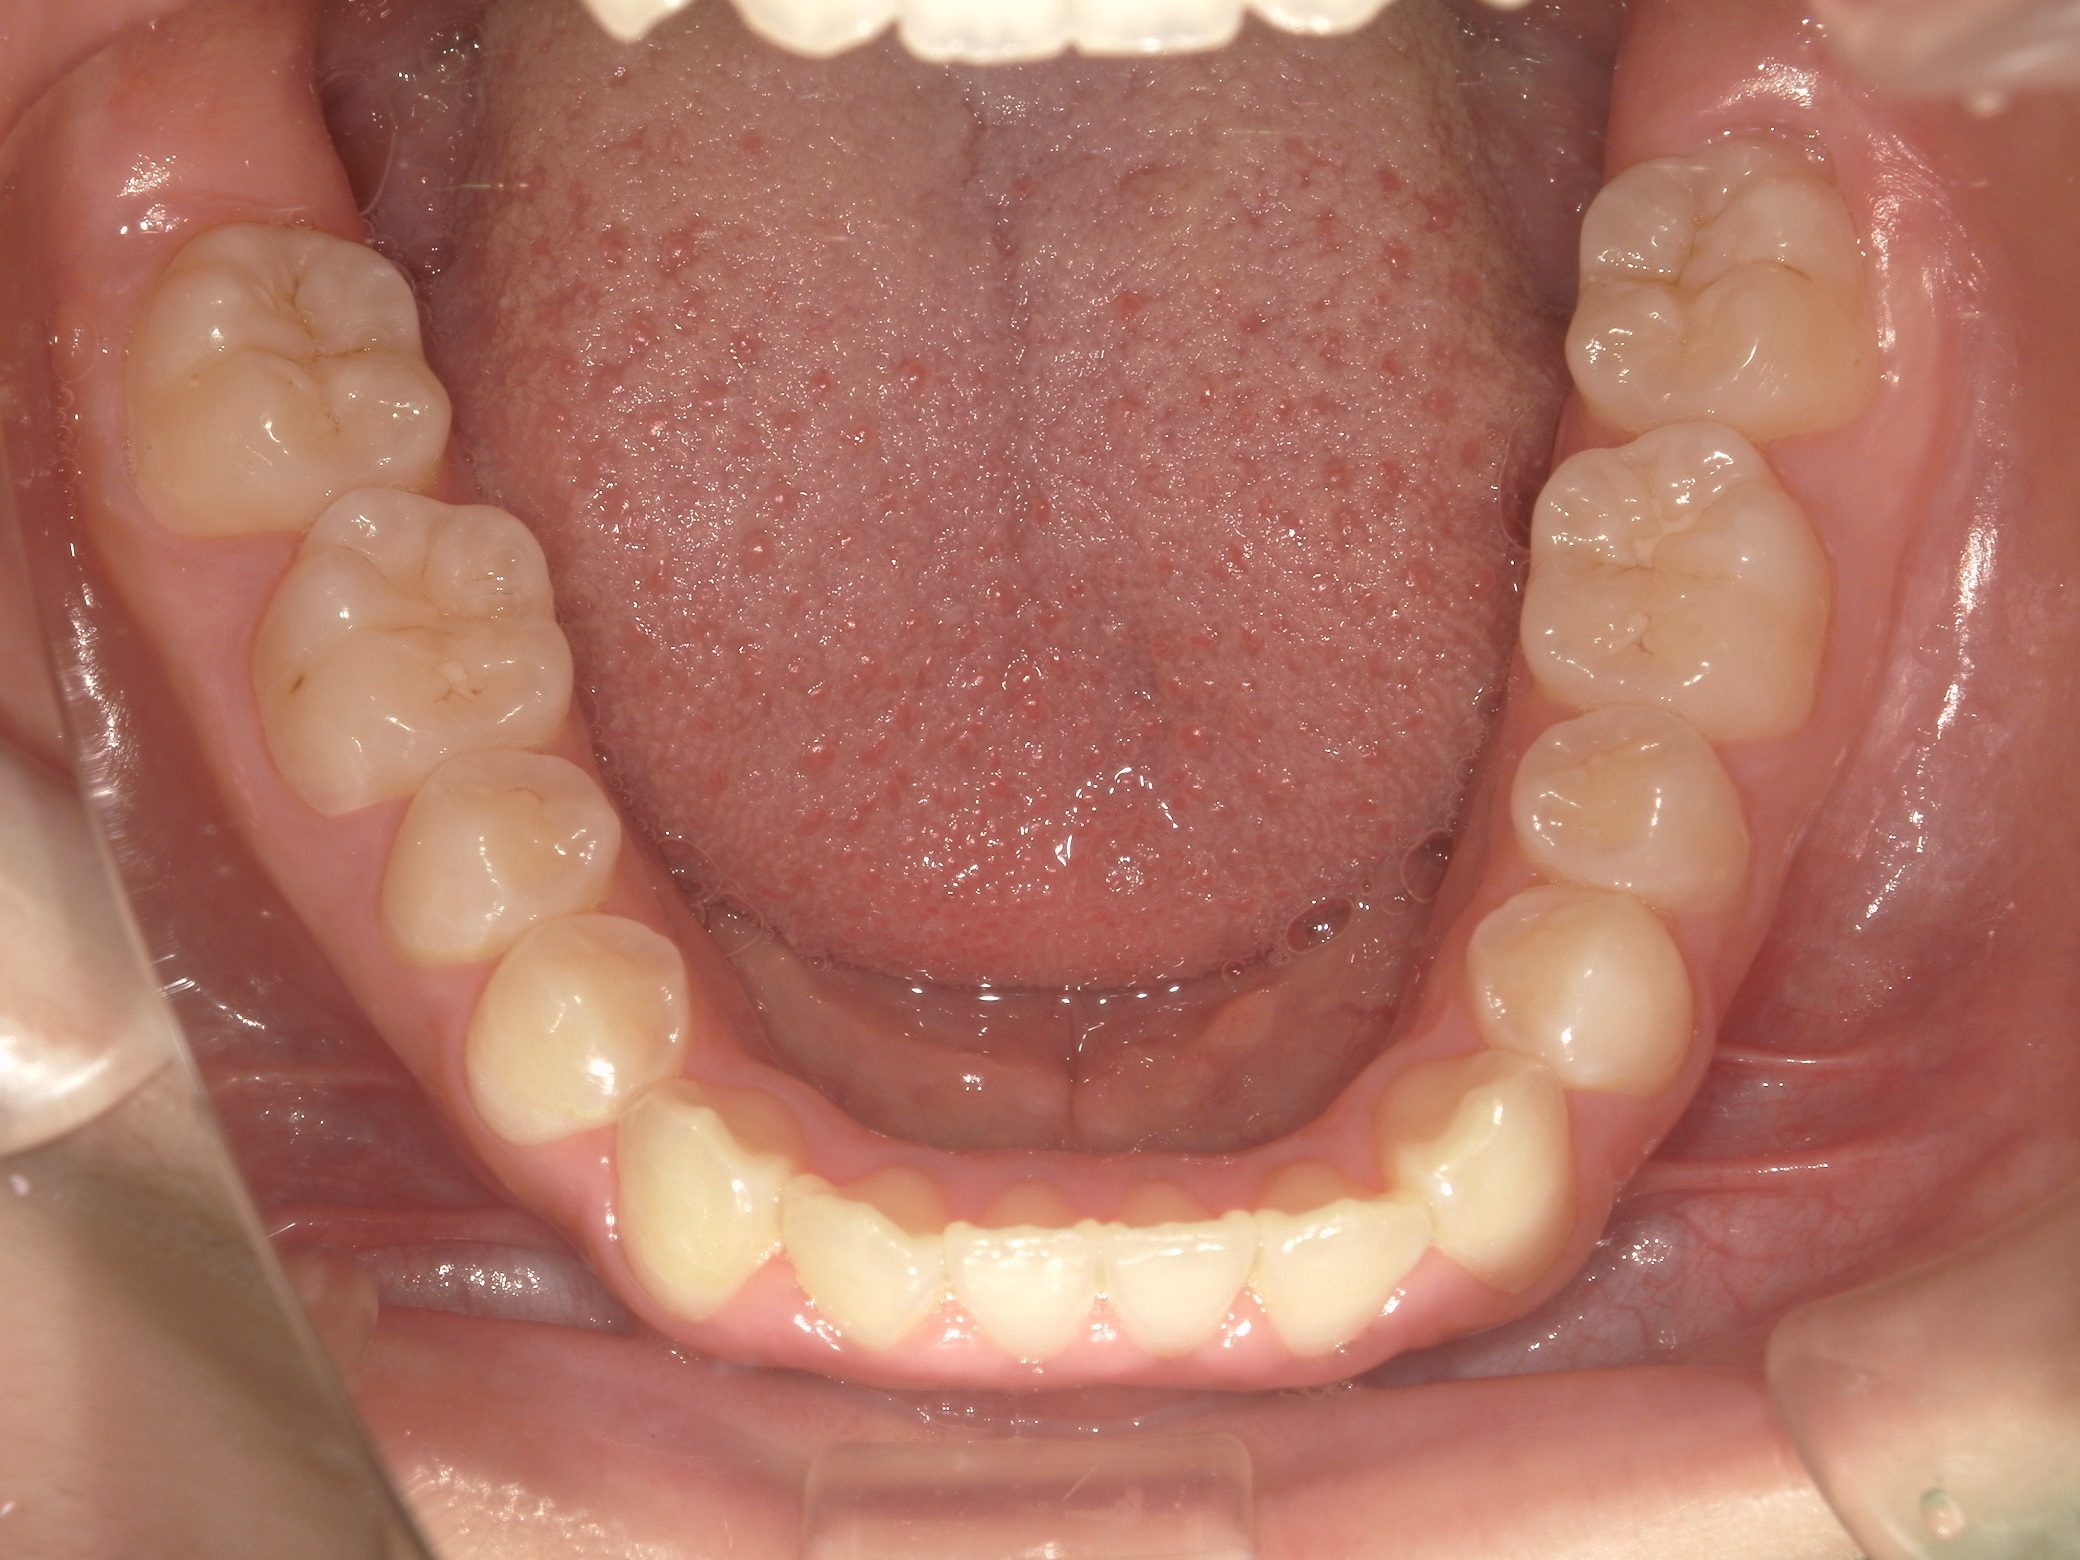

Before

After

【小学生】マイオブレース矯正➡ 【中学生】インビザラインフル 受け口 と 開咬 を改善

1期治療で 機能矯正装置と MFT 2年

2期治療でインビザラインフル 2年 をした患者さんです

もともと 舌癖があって 開咬 と 受け口の傾向があり

小児矯正(1期治療)をしましたが、咬み合わせに惜しいところがあり、2期治療まで行いました。

最終的に非常に良い咬み合わせになりました。